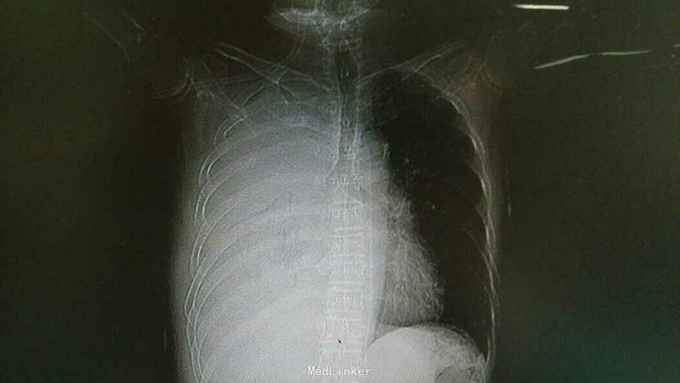

主诉:确诊肺癌7月余,气促1周 病史:患者因7月前咳血丝痰就诊广州中山大学肿瘤医院,胸部X片提示右肺癌并右肺炎症,阻塞性肺不张及右胸壁转移。予以胸膜活检提示:小细胞神经内分泌癌,予以VP16化疗。1周前出现气促,入住我科。

查体:慢性病容,右侧呼吸音低,左侧呼吸信增粗,可闻及湿性啰音。于无特殊。 辅查:胸部CT:右肺癌并右侧胸膜转移。

诊断:右肺肿瘤并阻塞性肺炎。 治疗:入院予以抗感染,止咳化痰,舒张支气管等治疗。